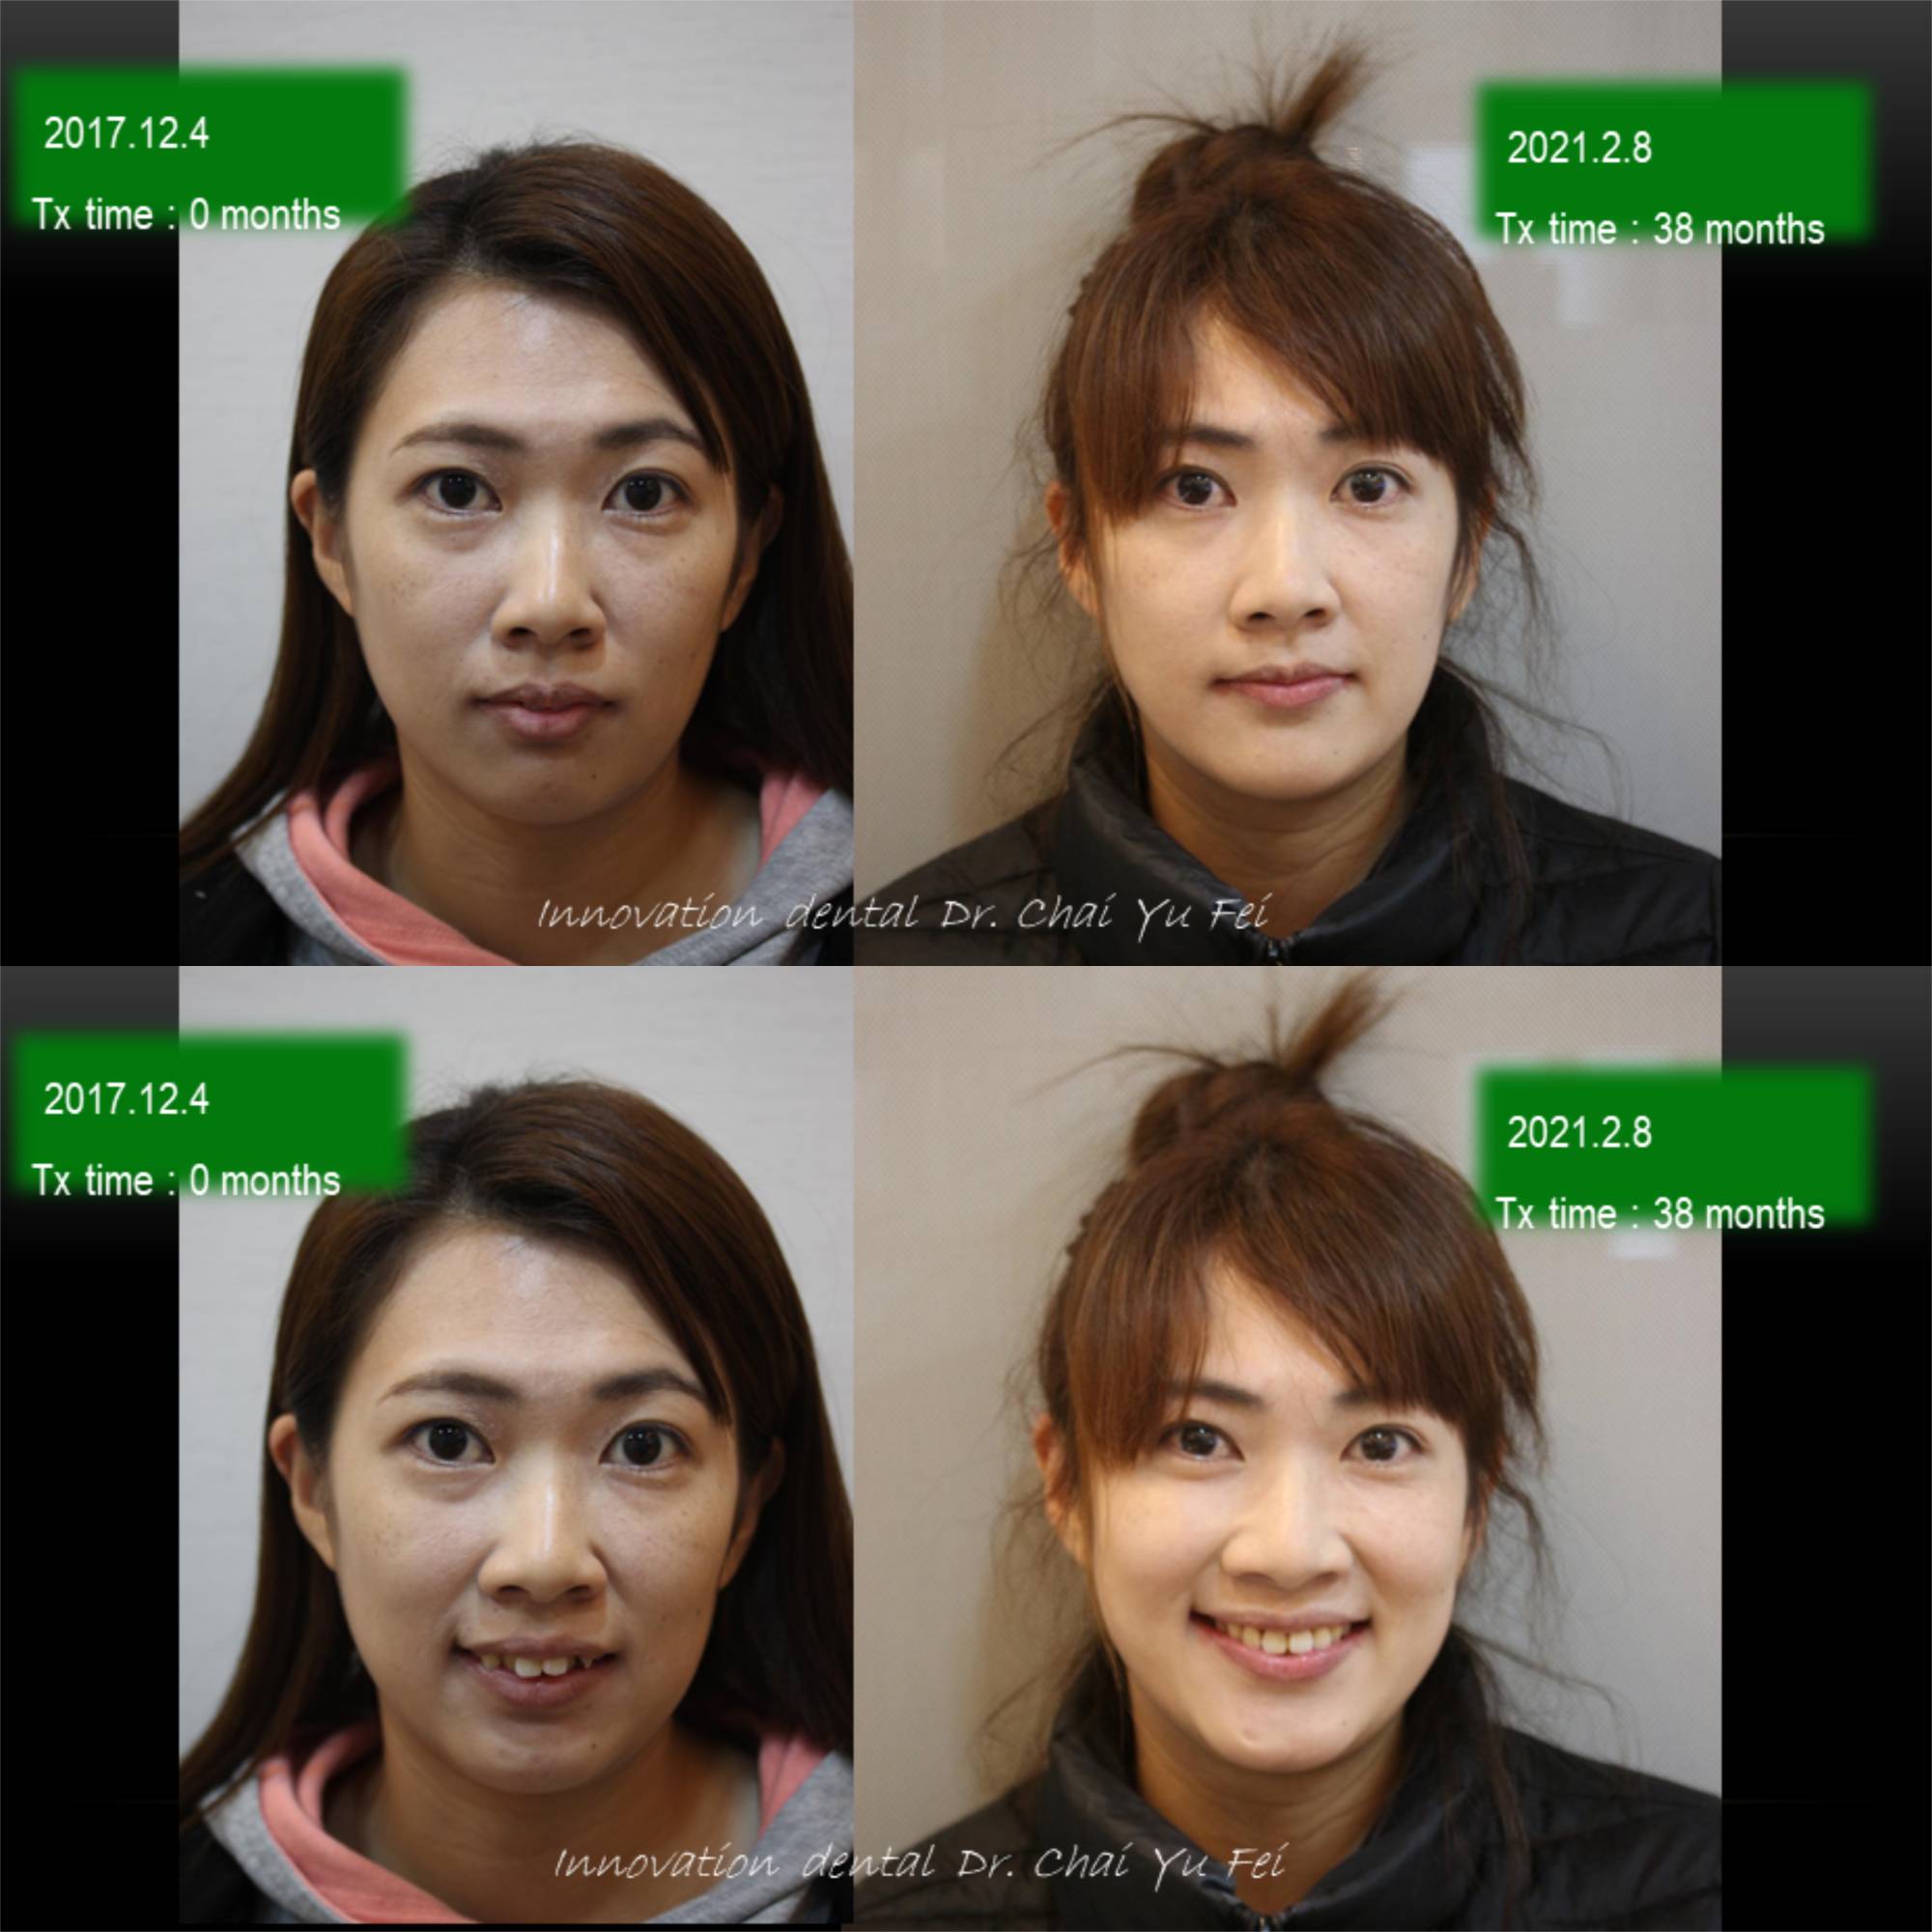

以這次黃小姐的案例來說,可以從照片中看到,由於上顎齒列狹窄,前牙角度往外傾斜,進而造成唇形前突不理想。

為了避免過度治療而傷害了原本可以恢復青春美麗的外觀,翟醫師決定採取上顎拔2顆小臼齒,下顎不要拔牙,在保留最多自然牙的情況下,改善下顎角度達到最美麗的外觀輪廓跟理想的咬合。

拔牙矯正前後變化,改善嘴型前突

看到這樣的治療結果,相信您應該對拔牙沒有那麼擔心了,不論是拔4顆或是拔2顆牙齒,我們無非都是為了讓出更多空間,來把齒列調整整齊,選擇拔牙的牙位通常也是重複性高的小臼齒,或是有病灶的牙齒,具有重要功能及不可取代性的牙齒我們不會隨便拔除,即使要犧牲牙齒,我們設計的治療計畫也會將犧牲降到最小,而且完全不影響功能以及外觀。治療完成後,一樣有好的微笑曲線跟理想穩定的咬合。